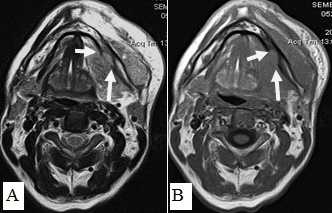

Не возникало сложностей в выявлении опухолевых узлов Т3, Т4 стадий, имевших все отмеченные выше признаки в различных сочетаниях в 36 исследованиях (рис. 11). Из 50 обследованных с помощью МСКТ и МРТ пациентов у 26 (52,0%) были выявлены метастазы в лимфатических узлах шеи. Поражались преимущественно лимфатические узлы I-II уровня. Признаками метастаза плоскоклеточного рака в лимфатических узлах были: увеличение размера лимфатического узла более 1,0 см, изменение формы лимфатического узла с бобовидной на округлую, структурные нарушения в узле, нечеткость наружных контуров узла, уплотнение окружающей жировой ткани на КТ или изменение сигнала на МРТ.

Рис. 11: А. МРТ полости рта, ротоглотки в аксиальной проекции. Рецидив опухоли языка размерами 6,0х6,5 см с распространением на дно полости рта, правую боковую стенку ротоглотки (стрелки). Выявляется переход за среднюю линию; В. Тот же больной. МРТ полости рта, ротоглотки в коронарной проекции. Опухолевый узел показан стрелками. Просвет ротоглотки сужен, деформирован. Опухоль имеет низкий сигнал на Т1-ВИ, аналогичный сигналу от окружающих мышц, при этом размеры опухолевого узла, его объемные характеристики позволяют четко отграничить от интактных тканей. Также отмечается структурная неоднородность патологического образования за счет некроза

Большинство пораженных метастазами лимфатических узлов имели размеры более 1,0 см, округлую форму (рис. 12). Внутривенное контрастирование при оценке изменений в лимфатическом узле являлось обязательным условием для уточнения внутренней структуры и выявления зон некроза. В результате гипоксии и распада ткани формируется центральная зона некроза, не накапливающая контрастный препарат при внутривенном болюсном усилении. При этом отмечается повышение плотности в периферических отделах лимфатического узла (рис. 13).

Рис. 12. Пациент П., 68 лет. МРТ полости рта, ротоглотки в коронарной проекции. Выявляется увеличенный подчелюстной лимфатический узел округлой формы, неоднородной структуры (стрелки)

Рис. 13. Пациентка К.,64 года. МСКТ ротоглотки, шеи в аксиальной проекции с внутривенным болюсным контрастированием. Рак языка с метастазами в лимфатические узлы средней яремной группы. Отмечается контрастирование пораженных лимфатических узлов по периферии, низкой плотности центральная зона некроза (стрелки). Билатеральное поражение